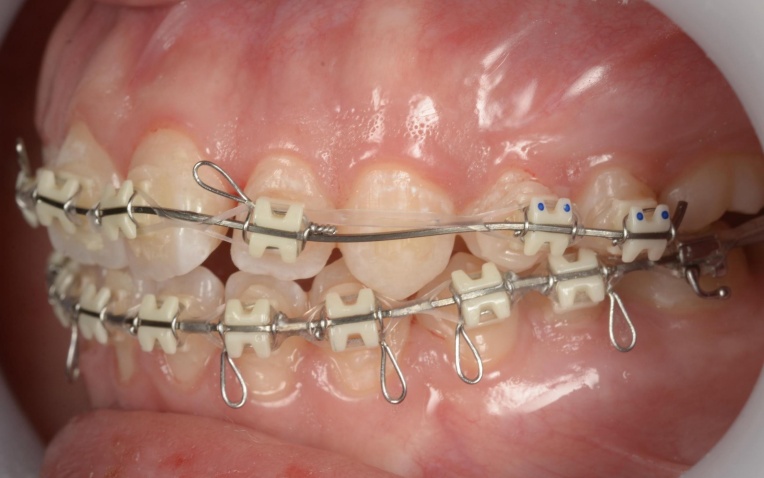

拝見したところ、重度の開咬(かいこう)が認められました。 |

| 治療内容 |

見た目と噛む機能の両方を改善するため、矯正治療を提案し、同意いただきました。 |